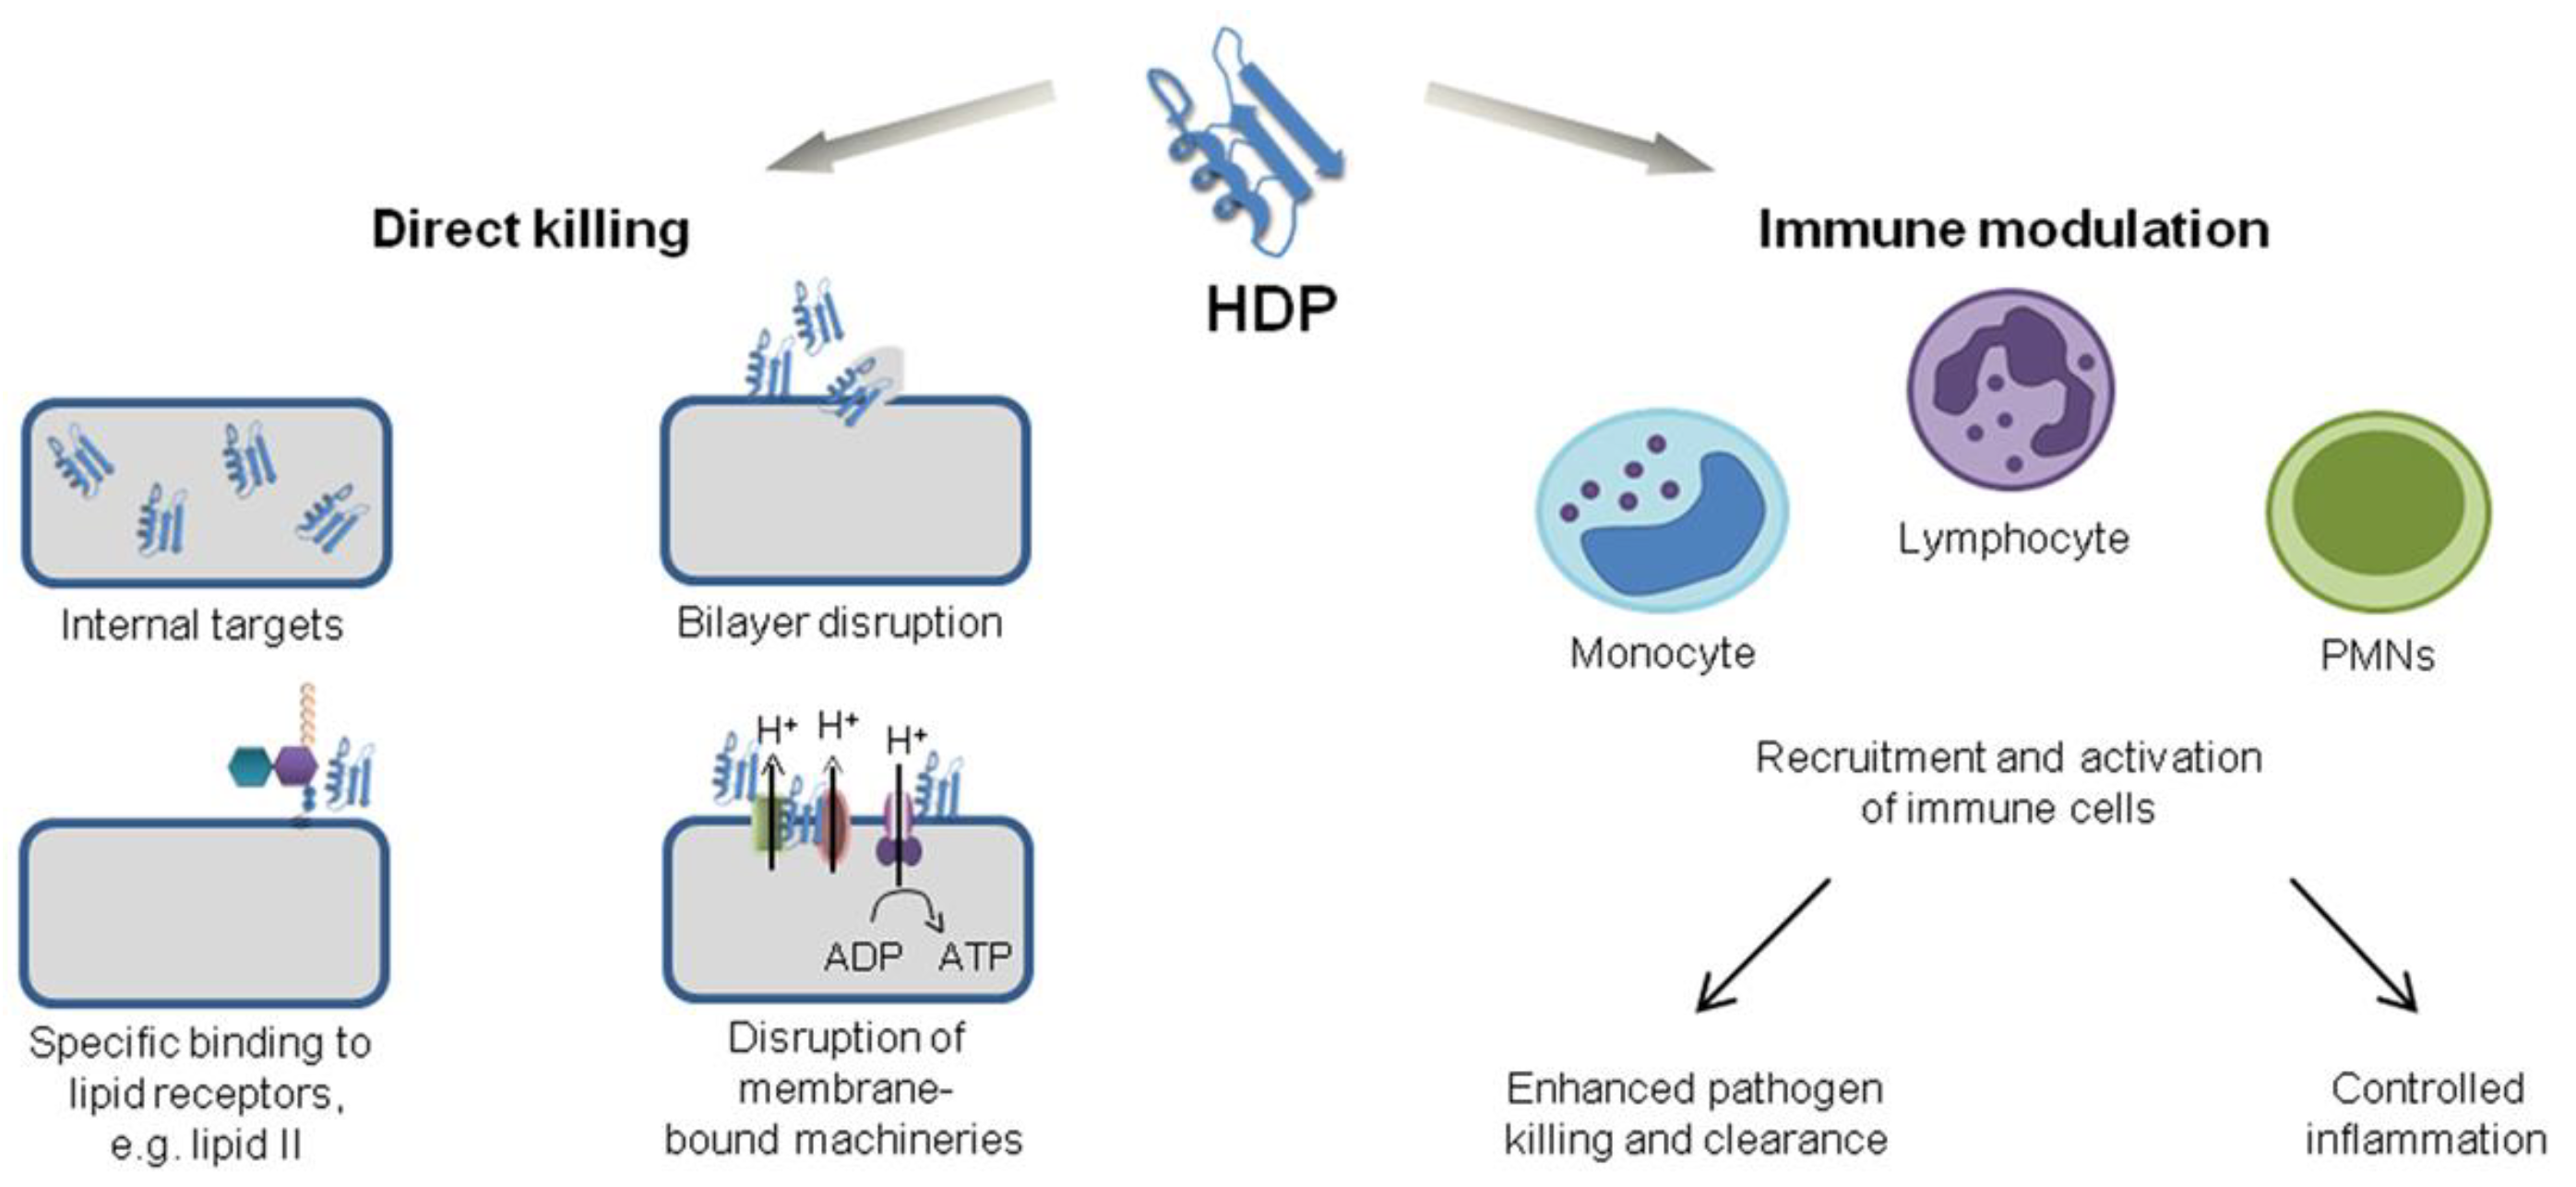

2. Chemical Structure and Mode of Action for AMPs